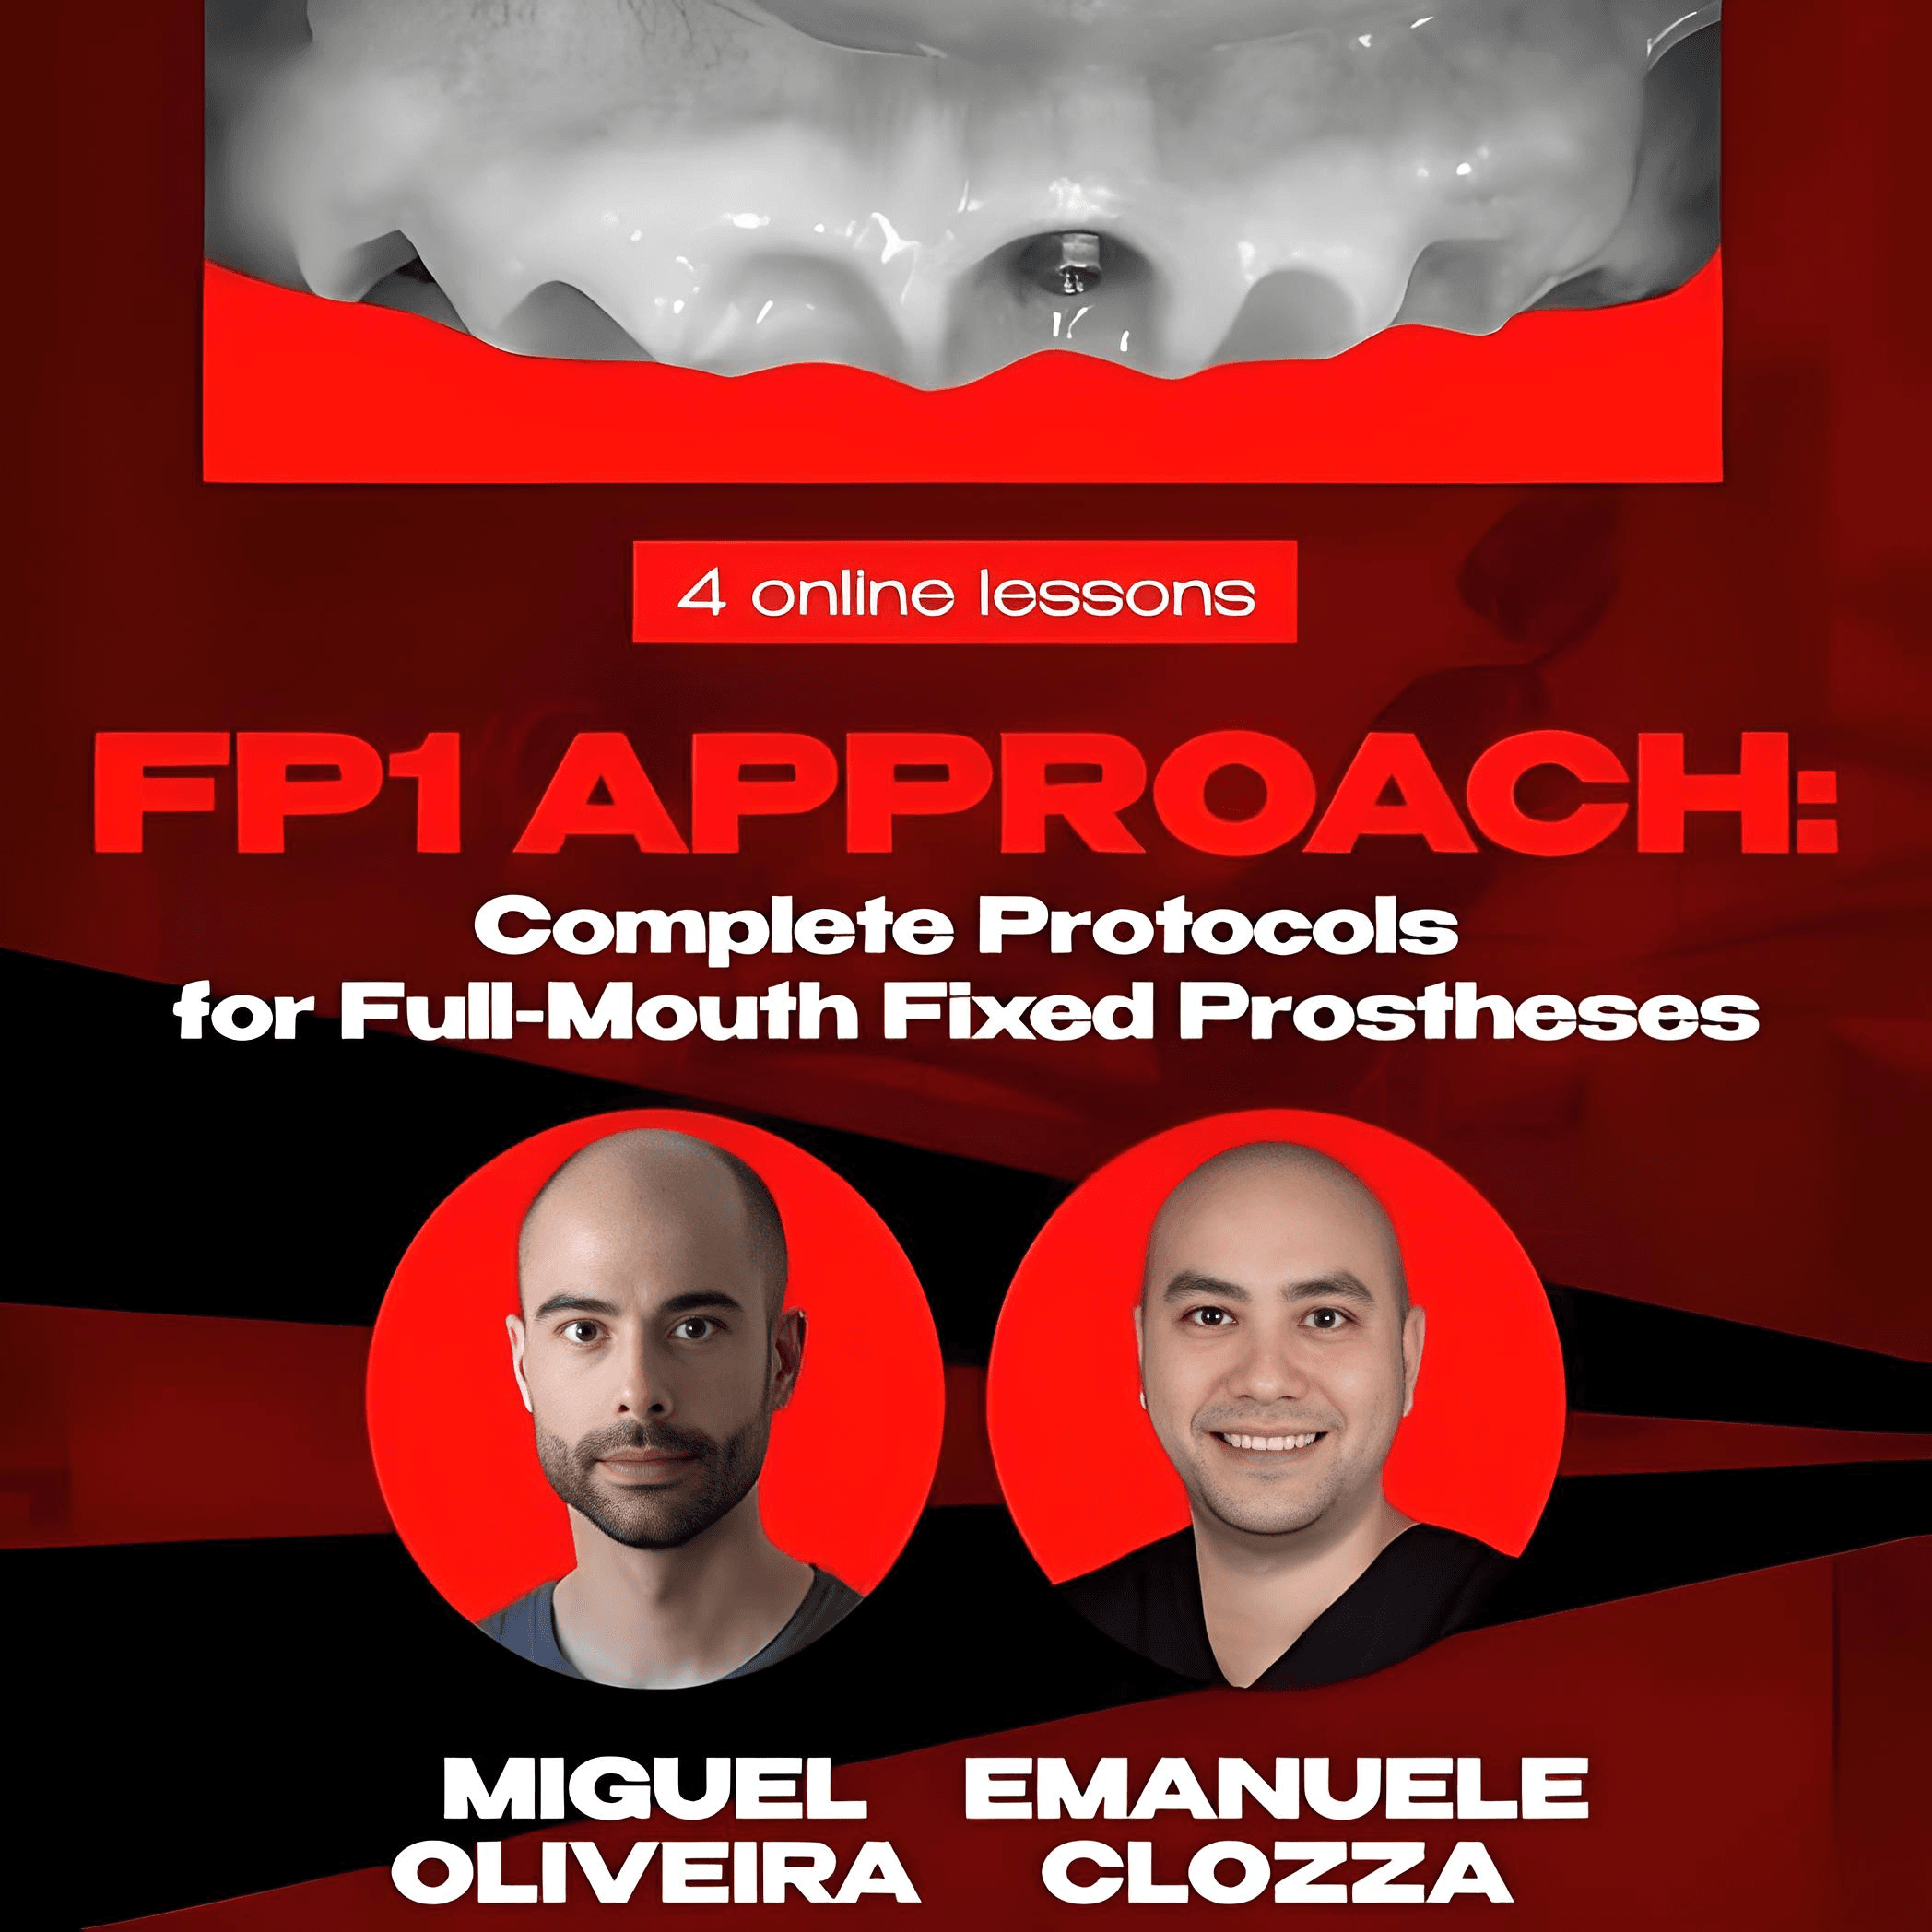

Course Overview

Comprehensive training on the treatment of complete edentulism with the FP1 approach by renowned implantology experts Dr. Miguel Mendes de Oliveira and Dr. Emanuele Clozza. This course provides complete protocols for FP1 treatment, enabling high-quality, aesthetic, and functional outcomes in full-mouth rehabilitations.

Course Details

Total Duration: 2 hours 51 minutes

Access Duration: ULIMITED

Lessons Included

- Lesson 1: FP1 Planning and Peri-Implant Workflow (38 min)

- Lesson 2: Perio-Prostho Approach to Aesthetic FP1 (47 min)

- Lesson 3: Advancements in FP1 Full-Arch Implant Restorations (36 min)

- Lesson 4: FP1 Full-arch Implant Restoration with Photogrammetry (50 min)

Instructors

Dr. Miguel Mendes de Oliveira

International Lecturer on advanced Implantology, Periodontics, and Guided-Surgery.

Dr. Emanuele Clozza

Extensive experience in All-on-4 concept, guided surgery, and full-mouth reconstruction.

Recommended For

Orthodontists, Prosthetists, Gnathologists, and General Dentists.